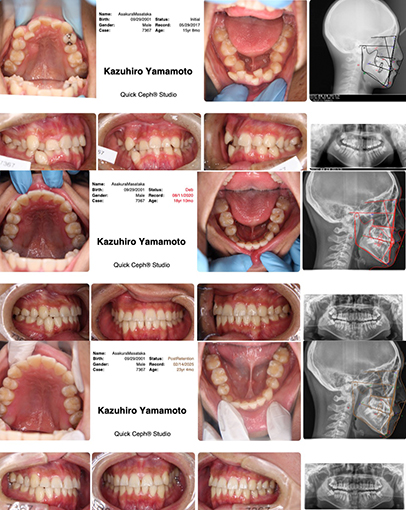

画像説明 : MY ①主訴 : 歯が出ている ②診断名あるいは主な症状 : 上顎前突症 ③年齢 : …

画像説明 : MY ①主訴 : 歯が出ている ②診断名あるいは主な症状 :  上顎前突症 ③年齢 :…